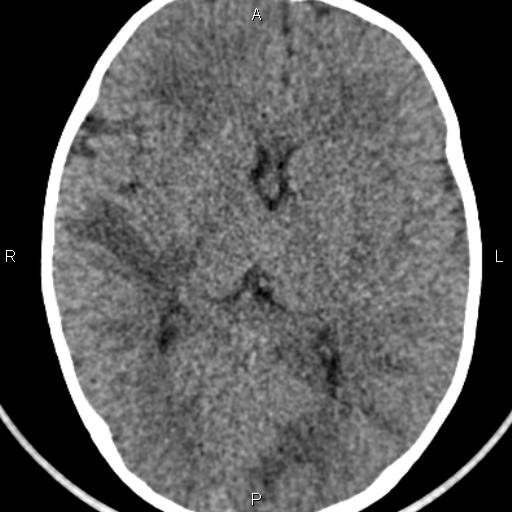

Демиелинизирующие заболевания мозга: МРТ изображения